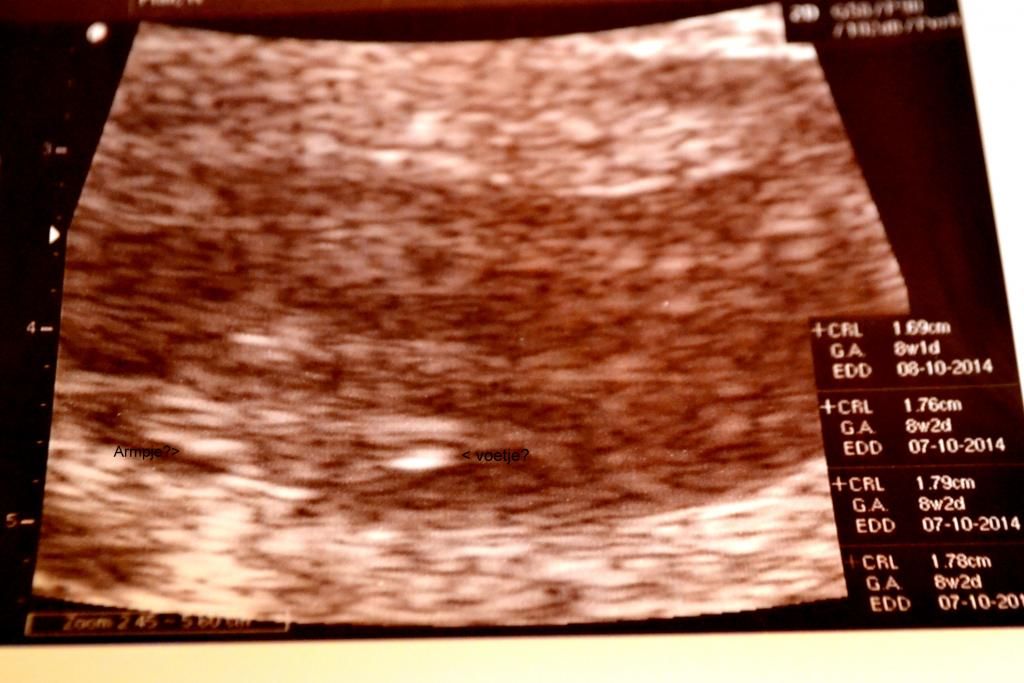

Handjes voetjes?

konden gelijk doorlopen. we vroegen kan het nu ook uitwendig, want van dat inwendige gedoe! had ze nu ook wel genoeg van, ja hoor geen probleem, hop gel erop en kijken maar. ff goed kijken inzoomen en JA hoor daar was je. je hartje klopt nog steeds super goed, en je bent 0,45cm gegroeit, je crl komt uit op 8 w 2 d, ietsje korter als 18-02-14 maar dat kon zijn door de uitwendige echo, inwendig was je ook beter te zien , en waarschijnlijk wat groter, maar dit was voor ons niet nodig je hartje klopt en je groeit, je was zelf iets aant bewegen zo schattig, ja viel kan je niet zien op de echo, maar voor ons genoeg,